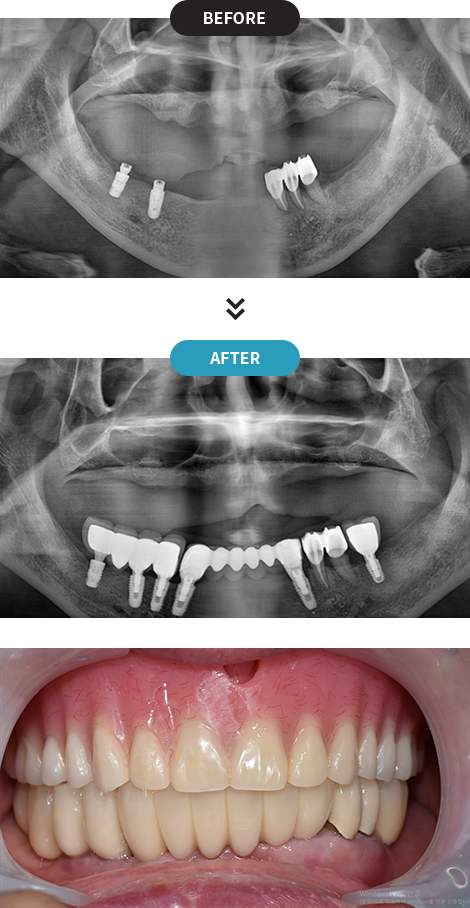

3D디지털 스캔을 활용하여 가장 안전하게 임플란트를

식립할 수 있는 위치를 0.1mm 오차까지 정확하게 계산합니다.

제작된 보철물을 모의 수술을 통해 정해진 임플란트 식립 위치에 빠르고 정확하게 식립합니다.